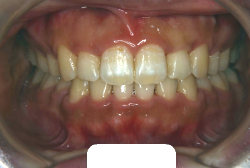

叢生(そうせい)

凸凹な歯並びのことを叢生といいます。矯正歯科に来院する患者様の主訴の中で、最も多いのが「配列の凸凹を真っ直ぐにしたい」というものです。歯の大きさと顎の大きさの調和がとれていないことが原因です。

凸凹を主体としたケースの場合、当院の平均治療期間は18ヶ月ですので、このケースは少し長めに経過しました。理由の一つは凸凹の程度がかなり重症だったと言うことですが、もう一つは、右下第2大臼歯が45度くらい前傾していたため、それを整直化させるために時間を要したと考えています。いずれにしても最終結果は大変よい状態と思います。

治療前は並びが乱れて見た目が悪いというのはもちろん問題ですが、歯科医学的に一番困るのは噛み合わせが悪いという点です。上下の犬歯(3番目の歯)は、上下的に離れた位置にあるため接触することができません。つまり歯としては存在していても、歯としては機能していないということです。